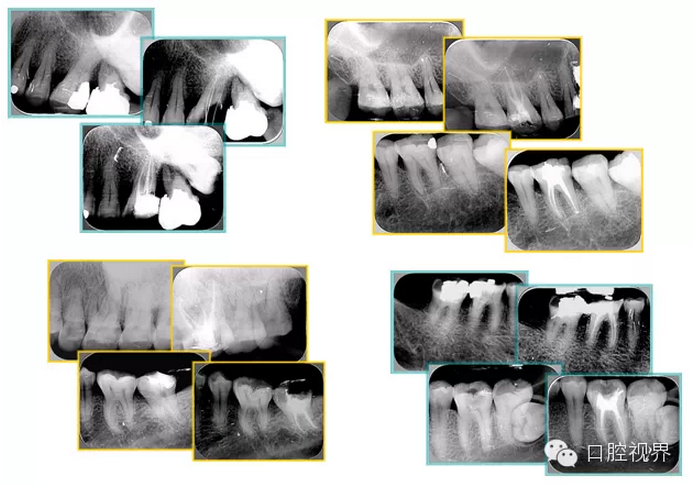

共有 4 張 X 線片,分別是術(shù)前、診斷絲 、主牙膠尖確認(rèn)、術(shù)后。

( 1 )術(shù)前:術(shù)前 X 線片用來(lái)了解牙齒的大概情況。術(shù)前預(yù)期為多根牙時(shí) X 線片應(yīng)偏頭拍攝。

( 2 )診斷絲:根據(jù)術(shù)前 X 線片進(jìn)行開(kāi)髓、根管的初步預(yù)備后,需要插入診斷絲,用來(lái)指示工作器械位置。常用 10 號(hào)或 15 號(hào)擴(kuò)大器作為診斷絲插入牙髓腔。

( 3 )主牙膠尖確認(rèn):通過(guò)術(shù)前預(yù)期和診斷絲診斷,明確工作長(zhǎng)度、牙根走向,進(jìn)行根管預(yù)備。之后應(yīng)進(jìn)行主牙膠尖(中銼)確認(rèn),已明確根管是否適合充填。

( 4 )術(shù)后:觀察治療效果。